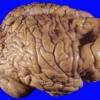

7A1 Porencephaly (Case 7) 2

7A2 Porencephaly (Case 7) 1

7A3 Porencephaly (Case 7) 3

8A1 Porencephaly and hydrocephalus (Case 8) 4